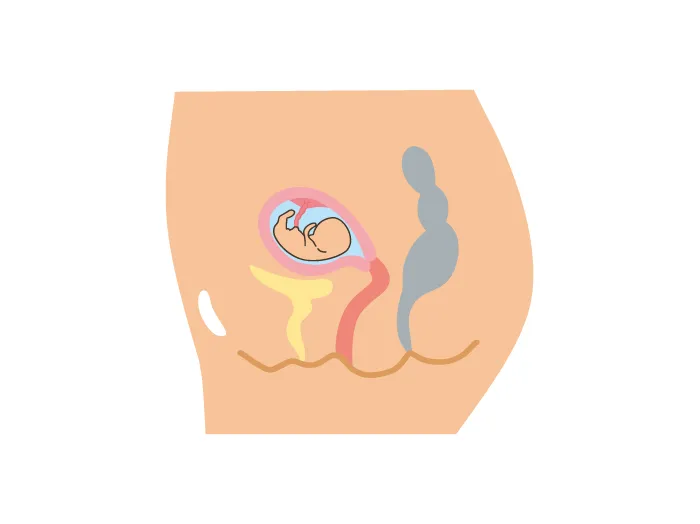

妊娠・出産による変化 その1 ~姿勢~東京都北区でお産ができる出産施設なら東京北医療センター産婦人科。

妊娠中のおなかの膨らみ方は?いつから変化する?どこから?-おむつのムーニー 公式 ユニ・チャーム。

妊娠16週から始まる妊娠5ヶ月目の胎児と母体の状態 16週、17週、18週、19週 -おむつのムーニー 公式 ユニ・チャーム。